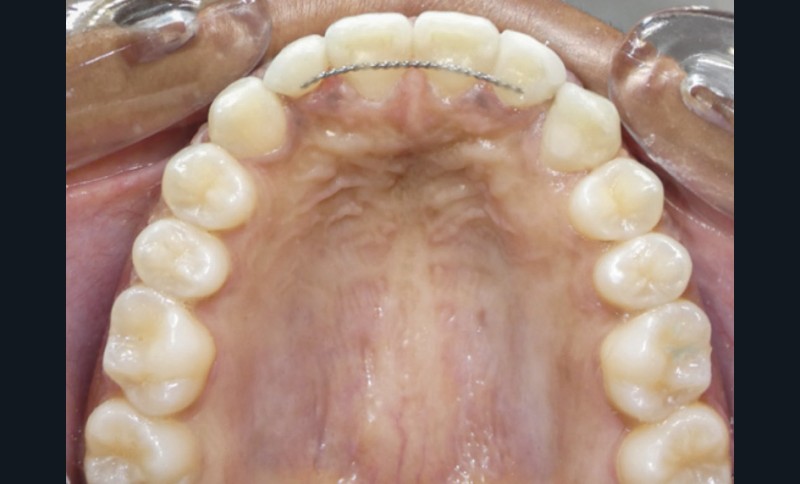

Correction de la denture

Le traitement orthodontique a été réalisé en technique vestibulaire multi-attaches 0,022’’ x 0,028’’. Après l’alignement et le nivellement de l’arcade maxillaire (arcs Niti 0,014‘’,0,018‘’, 0,017 x 0,025’’), un acier 0,019 x 0,025’’ a été mis en place. Un ressort Niti actif a permis de créer l’espace nécessaire pour accueillir la 23 sur l’arcade (fig. 3). L’espace nécessaire a été évalué par mesure de la réplique dentaire tridimensionnelle.